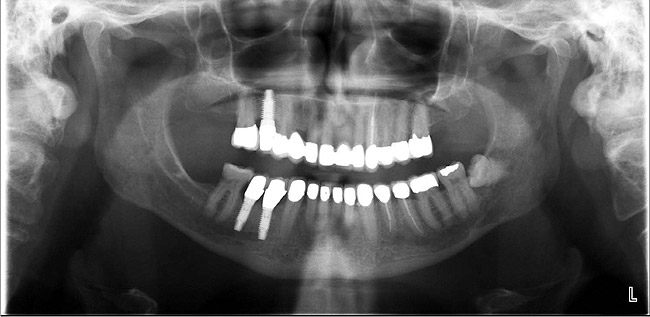

There are two treatment plans for a patient with advanced periodontal disease—one is set by the general practitioner, and the other is set by the periodontist—and for both of them to work as they should, communication must be open and often. They should look at radiographs together, plan treatment together, and set both short- and long-term goals for the patient.

Figure 4  A crown height space > 15 mm necessitates a hybrid restoration.

Figure 4